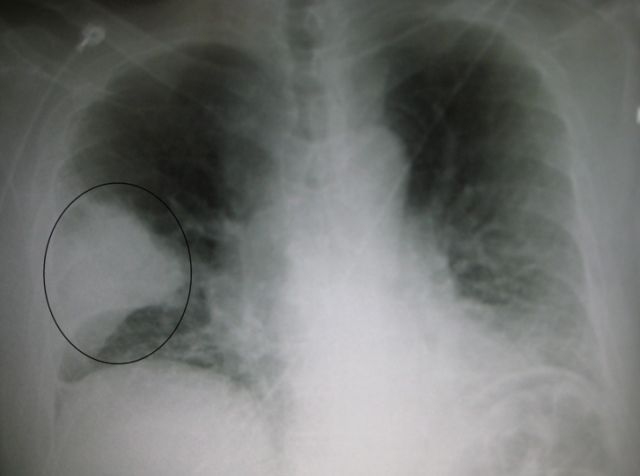

A fost observata, de asemenea, o legatura intre sanatatea orala deficitara si pneumonie, constatandu-se o incidenta mai mare a bolii la pacientii cu infectii parodontale decat la cei care nu se confrunta cu astfel de probleme. Explicatia porneste de la faptul ca plamanii se afla aproape de gura, astfel ca bacteriile dintr-o cavitate orala cu probleme pot fi cu usurinta aspirate in plamani, favorizand aparitia pneumoniei sau chiar a Bolii pulmonara obstructiva cronica (BPOC).